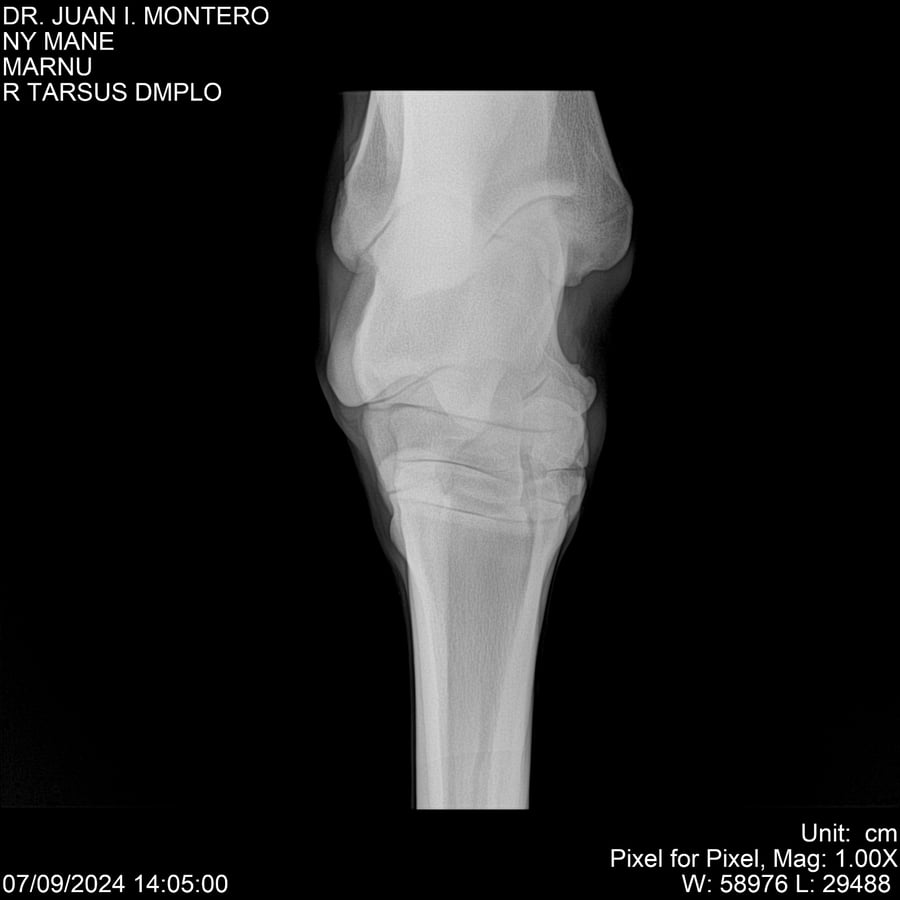

LOTE 20, NY MANE Lote Anterior Volver al remate Lote Siguiente Ficha Contacto Montevideo - Ficha del Lote Identificador: #282520 Categoría: Yeguarizos 76 Visualizaciones ClicData Contacto Empresa: Abelenda N. R., Walter Hugo Nombre*: Teléfono* : E-mail* : Mensaje Enviar Registrese gratis Este contenido Exclusivo está disponible sólo para usuarios registrados Ingresar